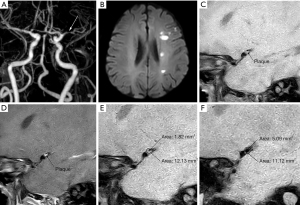

RI ≥1.05 was defined as PR (Figure 1); RI 0.96–1.04 was defined as non-remodelling; RI ≤0.95 was defined as NR (Figure 2). The plaque contrast enhancement grade was subjectively categorised as follows: grade 0—the enhancement was less than or equal to that of normal intracranial arterial walls in the same patient; grade 1—the enhancement was greater than that of normal intracranial arterial walls but less than that of the pituitary infundibulum; and grade 2—the enhancement was greater than or equal to that of the pituitary infundibulum (17).

In this study, patients with atherosclerotic MCA stenosis in the symptomatic group had a smaller LAMNL, larger PA, higher RI, more superior/posterior plaques, more obviously enhanced plaques, and a larger number of PR pattern than those in the asymptomatic group (Figure 2). Moreover, logistic regression analysis showed that the combination of PA, LAMNL, and the plaque enhancement degree had optimal predictive value for acute stroke. Our study also showed that HRMRI is a suitable method for depicting the features of vessel walls and plaques clearly without exposing patients to radiation injury, and it has extensive applications in intracranial artery diseases.